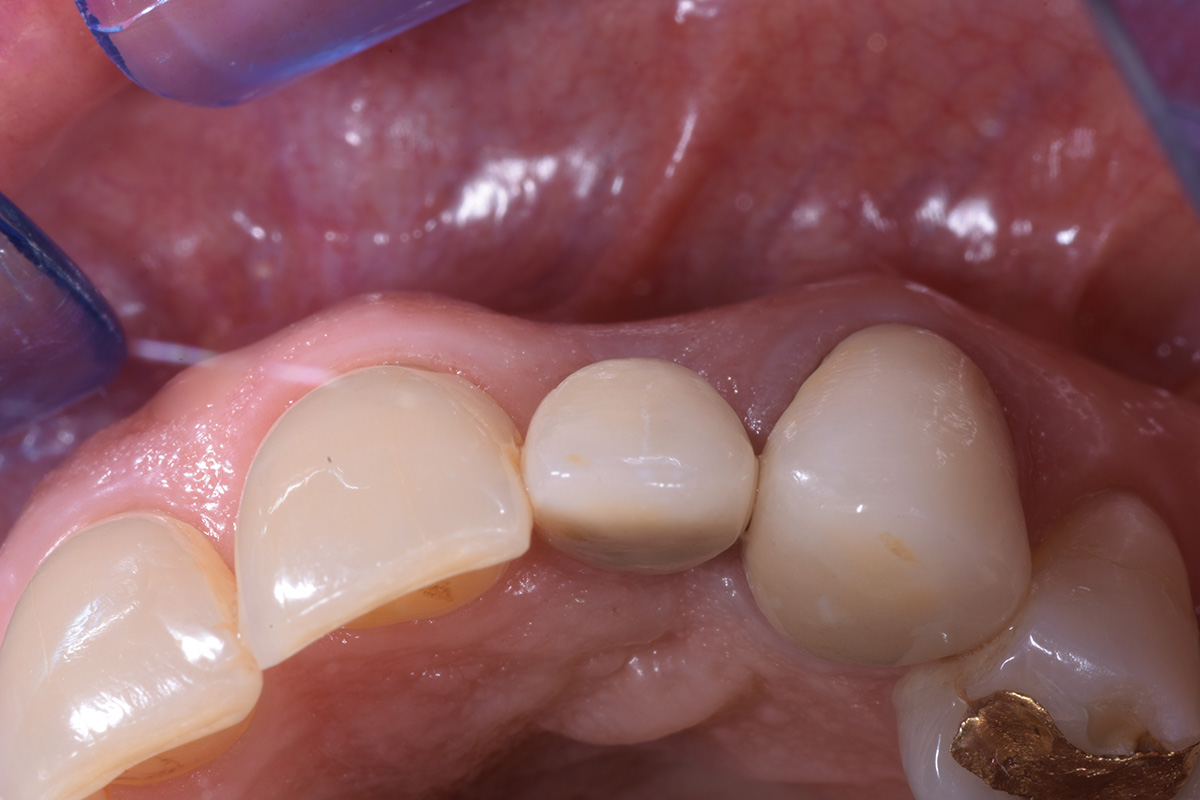

Correzione estetica mucogengivale, mediante innesto di connettivo, di esposizione impianto di incisivo laterale sup dx, con rifacimento protesico di laterale e canino.